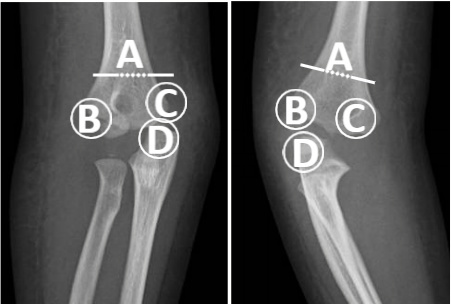

62.顯示此女童發生了何種骨折?

(A)肱骨髁上骨折(humeral supracondylar fracture)

(B)肱骨外髁骨折(humeral lateral condyle fracture)

(C)肱骨內上髁骨折(humeral medial epicondyle fracture)

(D)尺骨鷹嘴突骨折(ulnar olecranon fracture)